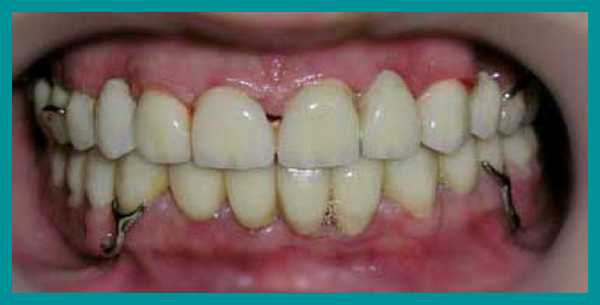

Пациент обратился с жалобами на истирание зубов верхней челюсти и, соответственно, снижение высоты верхних резцов до такой степени, что они перестали быть видны при улыбке. В результате клинического обследования челюстно-лицевой области не выявлено мышечно-фасциальных напряжений, движения нижней челюсти были в полном объеме, симметричные, патологических изменений со стороны ВНЧ сустава не выявлено. Прикус прямой (рис. 1) . На фронтальных зубах верхней челюсти 13—23 определяются окклюзионные фасетки истирания, клиновидные дефекты в области 24 и 25 зубов (рис. 1, 2). Высоту нижних зубов не планировалось изменять, хотя на них также имелись окклюзионные фасетки истирания, но с небольшой потерей тканей (рис. 3, 15) , поэтому прикус повышался без трансверсальных и сагиттальных перемещений нижней челюсти, а именно — в привычной окклюзии только за счет увеличения высоты верхних зубов.

При втором посещении планировалось завершить протезирование, но, когда время приема перевалило за 5 часов, решено было реставрацию двух оставшихся зубов, 32 и 33, перенести на следующий прием. Препарирование также было малоинвазивным (рис. 13—15) . В третье посещение работа была закончена (рис. 16, 17) .